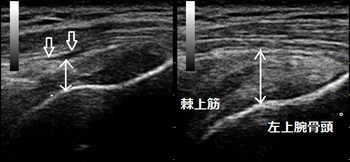

左肩上部 右肩上部

首や肩、背中の筋肉が全体的に硬くなっています。両肩の痛い箇所を指で押すとコリコリした部分を触知

します。その部分を超音波観察すると筋肉と筋膜や筋肉の一部が硬く癒着していました(画像丸の囲み)。

硬く癒着した筋肉などは放っておいても自然に柔軟になりません。軟部組織の癒着を丁寧に取り除く

リリース治療を行います。